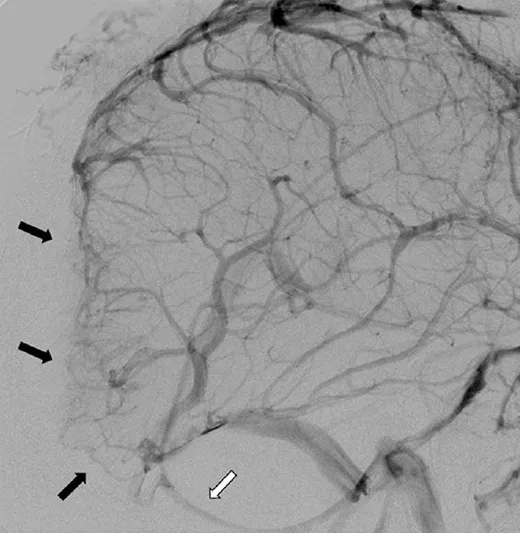

术前诊断性检查包括头颅磁共振成像(MRI)及磁共振血管成像(MRA),结果显示直径11.5厘米的肿瘤病灶跨越幕上及幕下区域,向双侧顶叶与枕叶延伸,并侵犯上矢状窦、窦汇及横窦近端。肿瘤经颅骨侵犯至枕部头皮及真皮层。脑血管造影显示上矢状窦、窦汇及横窦近端部分节段血流消失,深部静脉经枕窦引流,皮质静脉经增粗的Labbe静脉引流。

术前治疗方案包括对颈外动脉的肿瘤供血动脉进行栓塞处理,主要栓塞对象为枕动脉和脑膜中动脉分支,使用弹簧圈及聚乙烯醇颗粒作为栓塞材料。初步病理检查通过小切口切开活检实施,病理分析确认为世界卫生组织(WHO)I级脑膜瘤。